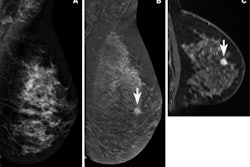

The researchers noted that CEM and MRI have a higher cancer yield than conventional breast ultrasound. However, previous studies suggest that CEM has similar detection to MRI with the added benefit of improved specificity. Prior studies also suggest that CEM is better tolerated among women.